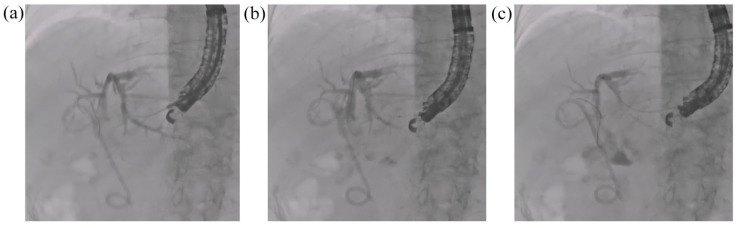

Background: Interventional endoscopic ultrasound (I-EUS), including EUS-guided biliary drainage, is now widely performed, but it becomes challenging if the visibility of devices is inadequate. A novel visibility enhancement mode, termed "Accent mode," has recently become available for use with a fluoroscopic system.

Objective: To compare the visibility of each device and pancreato-biliary ducts between Accent mode and Original mode during I-EUS.

Results: Twenty patients (Accent group) and 24 patients (Original group) were enrolled. Mean guidewire visibility scores were significantly higher in the Accent group (4.95 and 4.95 in the expert and trainee observers, respectively) than in the Original group (2.53 and 2.32, respectively; p < 0.001). For the dilation device, visibility scores were significantly higher in the Accent group (4.47 and 4.58 in the expert and trainee observers, respectively) than in the Original group (2.68 and 2.53, respectively; p < 0.001). Stent visibility scores were significantly higher in the Accent group (4.16 and 4.32 in the expert and trainee observers, respectively) than in the Original group (2.89 and 2.68, respectively; p < 0.001). Procedure time was significantly shorter in the Accent group than in the Original group (10.3 vs 17.2 min, p = 0.0012).

Conclusion: In conclusion, Accent mode appears to reduce I-EUS procedure time. It is necessary to confirm these findings in a prospective, randomized, controlled trial.